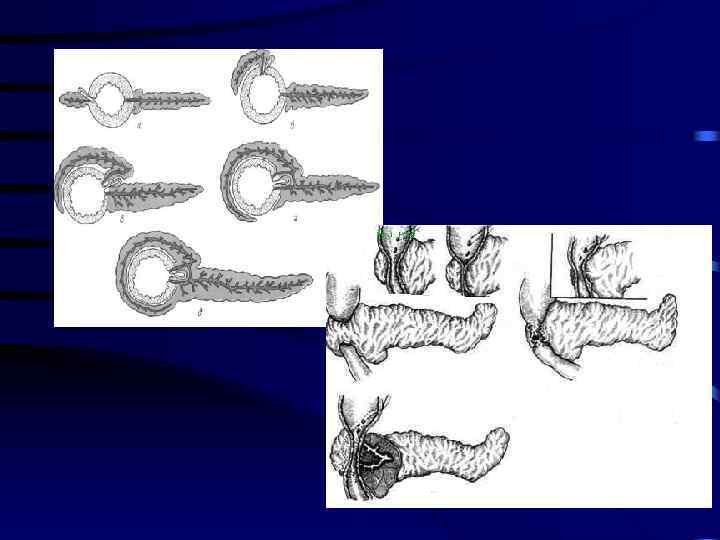

Кольцевидная поджелудочная железа • Врождённая аномалия ПЖ, при которой ткань ПЖ в виде воротника опоясывает двенадцатиперстную кишку, на разных уровнях суживая ее нисходящую часть

Методы лечения • • Дуодено дуоденоанастомоз Дуодено еюноанастомоз Гастро еюноанастомоз Пилоросохраняющее выключение ДПК из пассажа пищи по Ру • Удаление аберрантной поджелудочной железы.